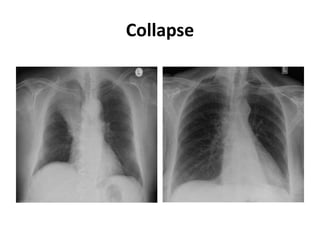

Collapse